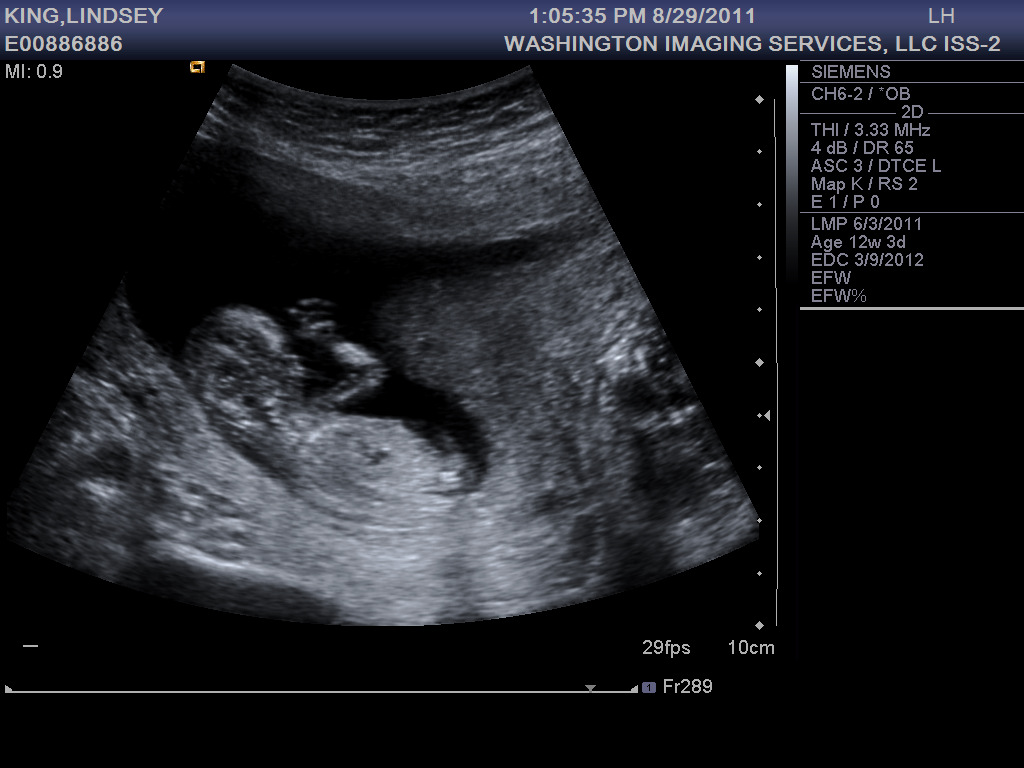

At my ultrasound last week, baby #3 was 13 weeks along and looking healthy and active. He or she was moving around so much the tech had to work extra hard to get measurements. Is this an indication of what to expect later on?

The first trimester is behind me now, thank goodness. So far I’m still exhausted and nauseous, but I expect these symptoms to wane in the coming weeks. Did I mention how T-I-R-E-D I’ve been? By 2pm I just want to crawl into bed in the fetal position, but there are still hours left until Jonathan’s home, then there’s dinner, putting the boys to bed, and by the time we finally hit the hay, I can’t fall asleep! So I toss and turn like a rotisserie chicken until at last sleep comes. But even then I wake up several times in the night, never really getting that sweet REM sleep… and then it’s time to get up and do it all over again. Okay, I’ll stop complaining now. I had it easy the first two times around, I should be thankful. And really, it could be a lot worse. On the up side, I get to spend my days with the two sweetest little boys in the world!

13 week bump shot